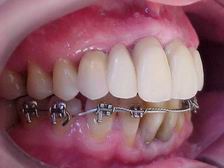

Extrusão completa do canino reanatomizado trans-cirurgicamente

Lado esquerdo: Alinhamento e nivelamento em evolução